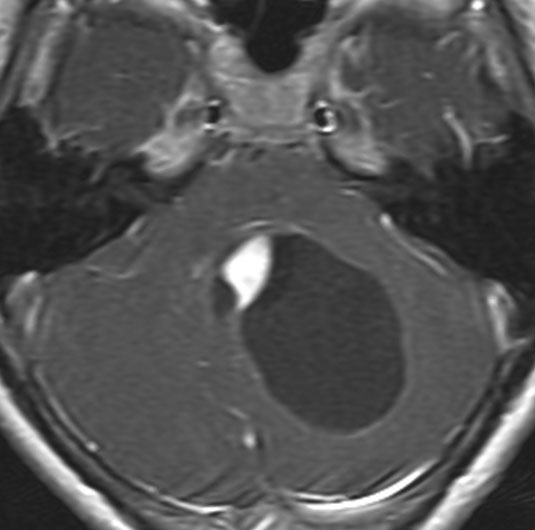

眼窩内に限局する視神経膠腫:神経鞘腫と鑑別が難しいもの

主訴は進行性の眼球突出です。視力低下は軽度で,視野欠損は左眼の下半分でした。入院前の画像では眼窩内神経鞘腫を疑う画像でした。

しかし,CISSの画像では中枢側の視神経との連続性があり,これではじめて視神経膠腫と診断できました。もちろん毛様細胞性星細胞腫です。眼球,眼球運動,眼瞼の動きを温存して腫瘍を眼球後極から切断して全摘出しました。